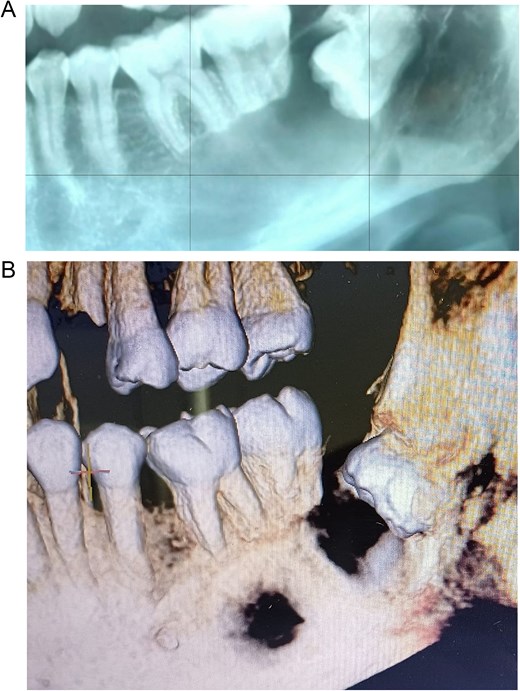

A 43-year-old female with no significant medical history was referred following the incidental radiographic detection of a unilocular radiolucent lesion in the left mandibular angle associated with a horizontally impacted third molar. Clinical examination revealed no pain, inflammation, or neurosensory alterations. Panoramic imaging (Fig. 1A) and cone-beam computed tomography demonstrated a well-defined lesion at the cemento-enamel junction, with cortical thinning, buccolingual expansion, inferior alveolar canal displacement, and root resorption of adjacent molars (Fig. 1B). The differential diagnosis included unicystic ameloblastoma and odontogenic keratocyst.

Preoperative imaging studies. (A) Panoramic radiograph. (B) Cone beam computed tomography.